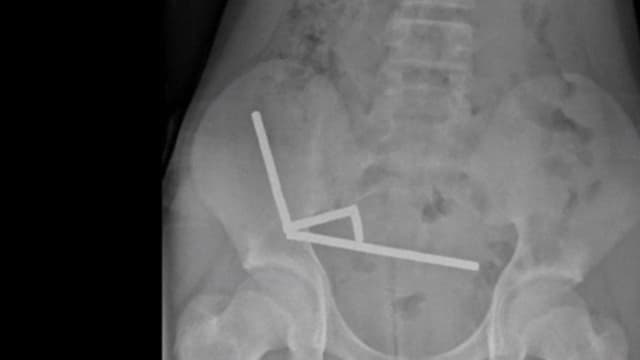

13さいの男の子、たくさんの強いじしゃくをのみこんで手じゅつ 13さいの男の子、たくさんの強いじしゃくをのみこんで手じゅつ ニュージーランドで、13歳の男の子が強い磁石を80個ぐらい飲みました。 お腹が痛くなって、病院で腸の一部を切る手術を受けました。 男の子が飲んだのは、ネオジム磁石です。 とても強い磁石で、大人が使うために売っています。 飲むと、磁石が腸などを引っ張って、穴があいたり、死んでしまったりすることがあります。 男の子は、TEMUというインターネットのサイトで磁石を買ったと言いました。 ニュージーランドでは、強い磁石を売ることを禁止しています。 TEMUは「今売っている磁石は、ニュージーランドの法律に問題がないものです」と言っています。